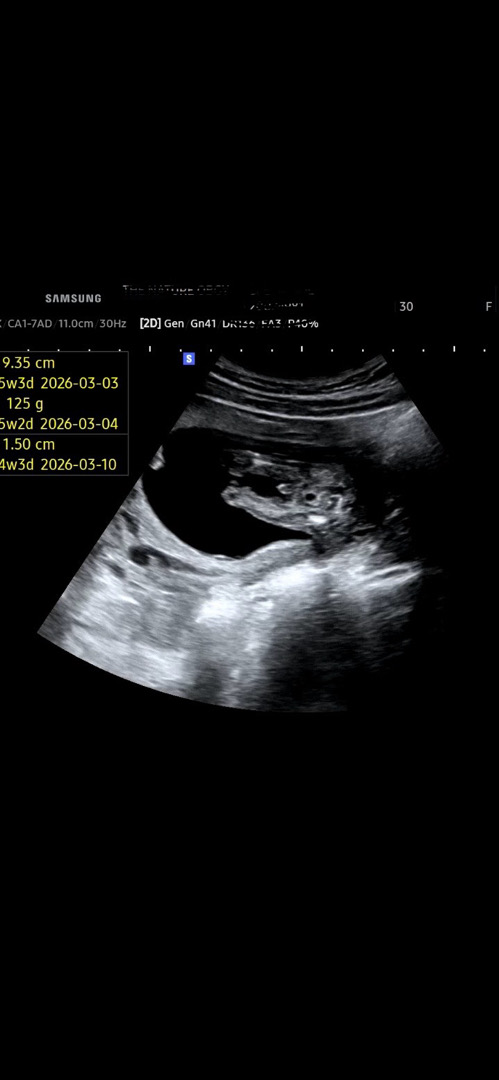

15주차 성별

15주차에 다리사이 그것이 보이는데,. 성별 바뀔일은 없겠죠..?

ㅎㅎ너무 확실한 그것...ㅎㅎ

남자애기입니다 ㅎㅎㅎ